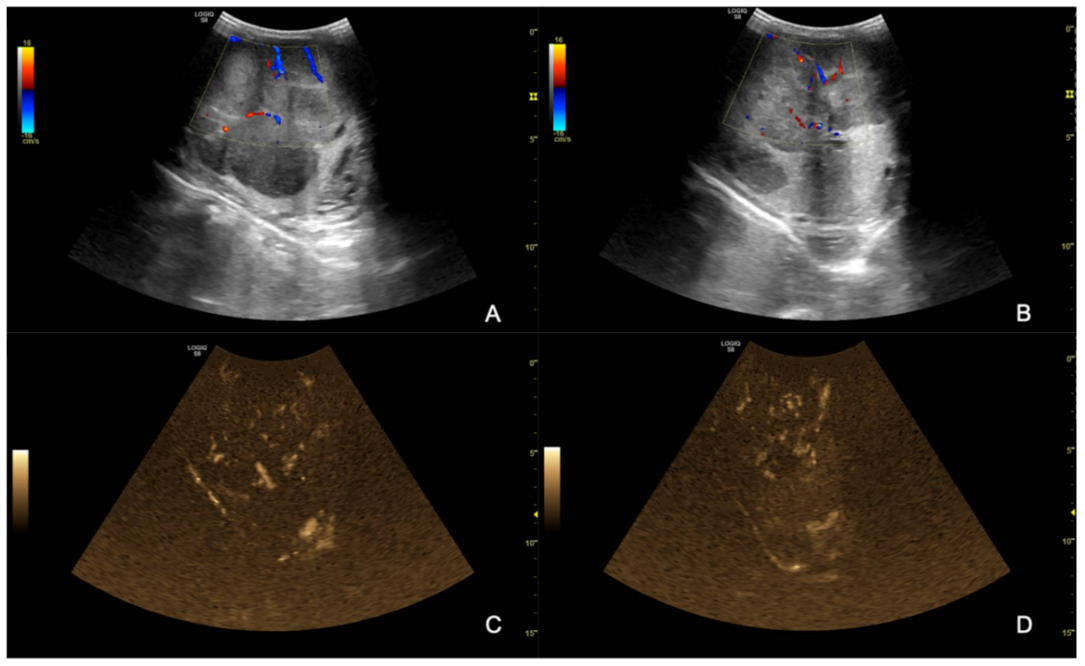

The ultrasound examination showed that the right testicle appeared normal (Figure 2), while the left testicle severely enlarged (13.35 cm CrCd × 8.19 cm DV × 9.42 cm LL vs. 9.25 cm CrCd × 4.75 cm DV × 6.91 cm LL). The parenchyma was characterized by the presence of multiple coalescing, nodular, well-defined and heterogeneous lesions of various size that almost completely effaced the normal anatomy and deformed the capsule or distorted normal shape (Figure 3); color Doppler and B-Flow evidenced a diffuse increase in vascularization, characterized by vessels of different size and localized both peripherally and in the central portion of the various nodular lesions, instead of normal unform vessel distribution from the capsule to the testicle mediastinum (Figure 4).

Figure 4. B-blow images (A,B) and Color Doppler (C,D) of the left testicle; note the heterogeneous vascular lesion distribution appearing as both peripheral and central in different portions of the same testicle.